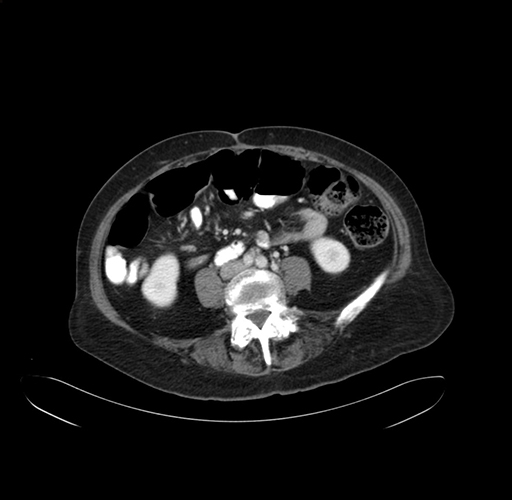

Pre-Chemo: Axial Venous

Axial Venous